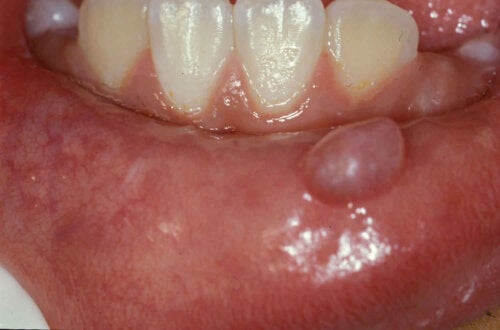

Мукоцеле или кисти на устната лигавица са честа причина за дискомфорт в устата при говорене или поглъщане на храна. Те се появяват като бучки или торбички по устните, езика, небцето или бузите. Интересувате ли се повече по темата? В следващите редове ще ви разкажем за проблема.

Понастоящем мукоцеле се счита за най-честата доброкачествена лезия в човешката уста. То не е нищо повече от малка киста, пълна със слуз, която се образува в областите, където има малки слюнчени жлези. Проучванията показват, че 96% от случаите на мукоцеле произхождат от долната устна.

Това са доброкачествени кистозни лезии, образувани от нарушение в малките слюнчени жлези. Те обикновено съдържат слуз и са покрити от мукозни клетки. Могат да бъдат повърхностни или дълбоки и да варират по размер от няколко милиметра до 3 сантиметра.

Мукоцеле се проявява внезапно като малък мехур или възел, пълен със слуз вътре в устата, обикновено на долната устна. Може да бъде с полупрозрачен син цвят или да поддържа същия тон на подлежащата лигавица. Тези лезии са безболезнени, освен ако не са придружени от рана.

Някои хора често ги бъркат с афти. Последните обаче са улцерозни лезии с червеникави ръбове и бели центрове, които причиняват болка и дискомфорт. Въпреки че най-често се появяват по долната устна, те могат да се образуват и върху езика, небцето, лигавицата на бузата и долната част на устата.